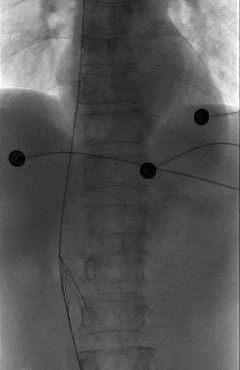

三个月后,滤器完成临时防护使命,阿婆按计划回到当地医院准备取出,可检查结果却让所有人犯了难——影像显示,滤器出现严重倾斜,大大增加了介入取出的操作难度,稍有不慎便可能造成血管损伤。

北京积水潭医院血管外科专家、郑州医院副院长田轩得知阿婆的就诊经历和身体情况后,第一时间为其专业评估,仔细查看影像资料,明确滤器倾斜的具体程度和位置,并告知阿婆及家属,可通过介入手段尝试取出,让阿婆悬着的心终于放了下来。

术中,团队在影像设备的精准引导下,娴熟操作介入器械,精准定位倾斜的滤器,避开血管周边组织,逐步完成滤器的调整、抓取与取出操作。